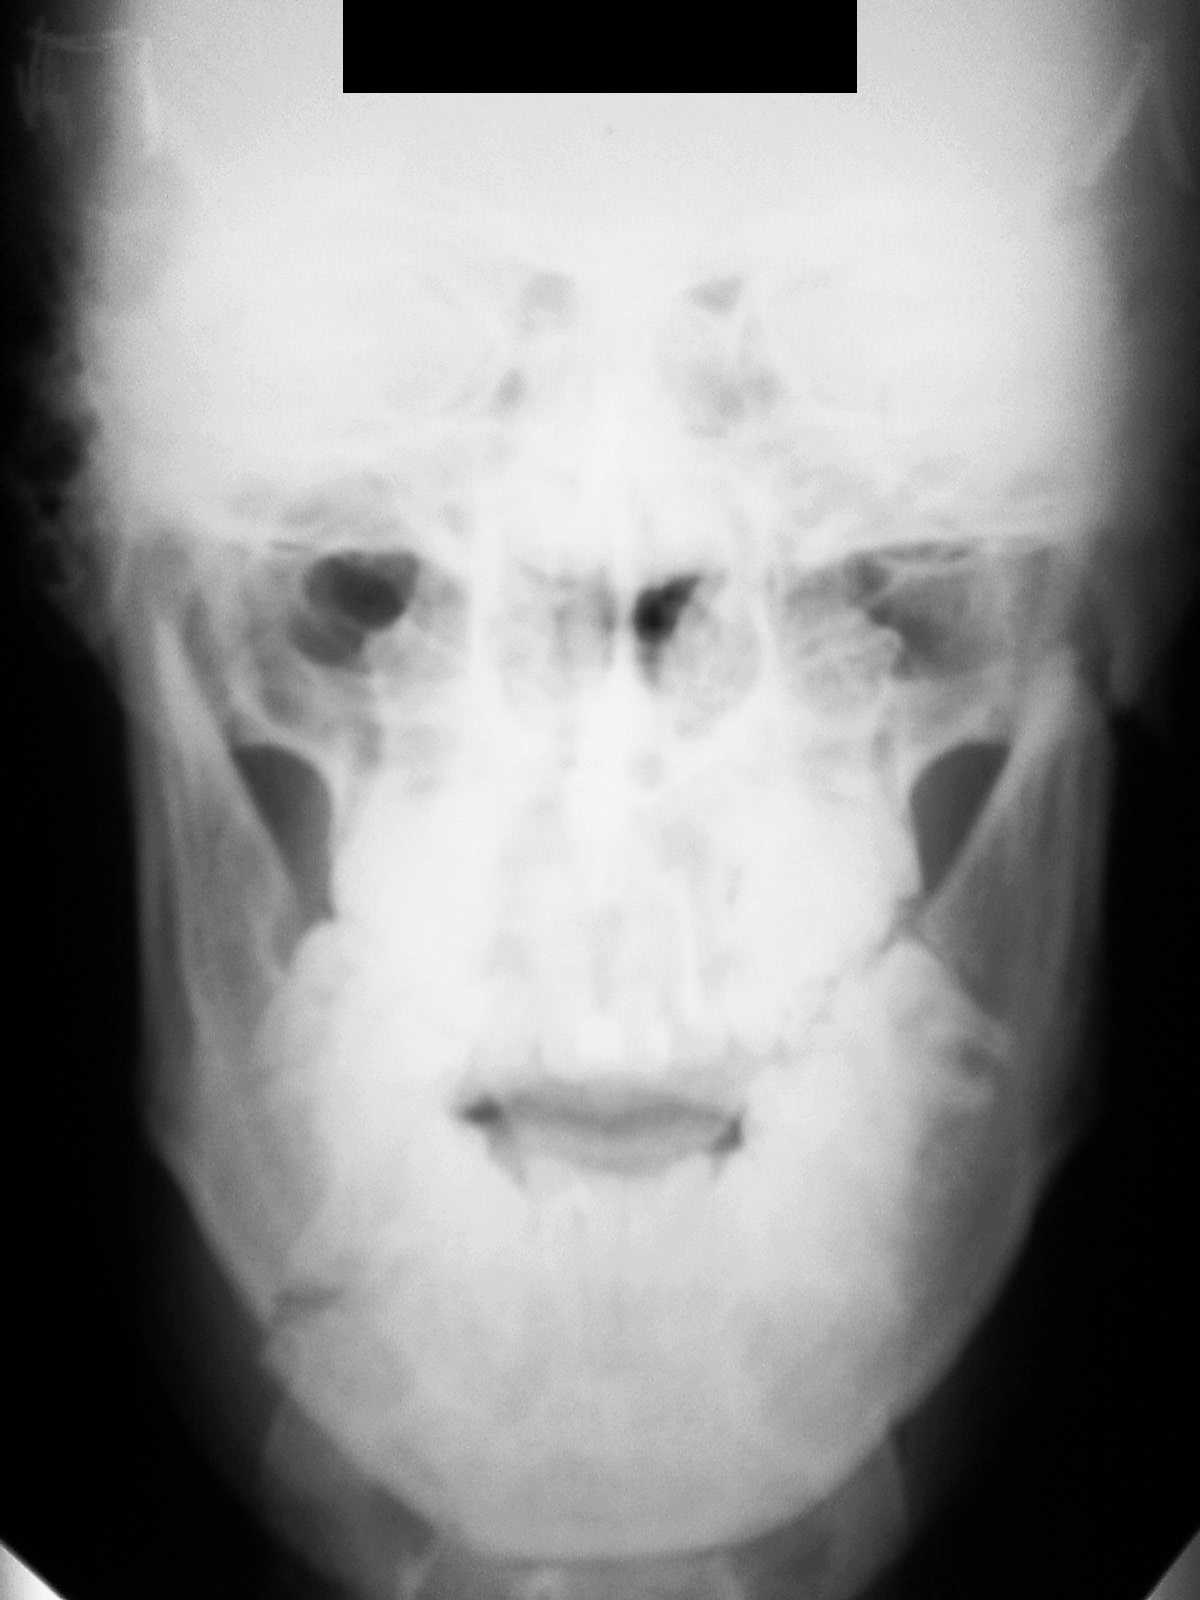

Зашинировали

У этого 3 г. назад нелеченная травма, теперь остеомиелит